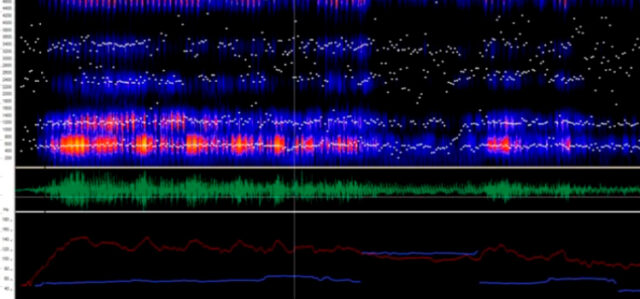

“Por lo pronto, los resultados generales en cuanto al estado de las cuerdas vocales y la ronquera de la voz, ya muestran variaciones apreciables respecto a personas no parkinsonianas. Esta investigación podría ayudar a que el médico determine si ya se precisa derivar al paciente, por ejemplo, a un fonoaudiólogo para trabajar los efectos que provoca esta enfermedad en la respiración, fonación, articulación y prosodia”, señaló Giuliano en diálogo con Agencia CTyS-UNLaM.

En paralelo, un grupo de estudiantes del Departamento de Ingeniería e Investigaciones Tecnológicas de la UNLaM se enteró del proyecto y desarrolló un sistema de software libre llamado “Parkinsoft”. Esta herramienta, que surge del trabajo colaborativo, permitirá que los médicos realicen el seguimiento de los pacientes con EP a través de plataformas web y mobile, incluso a distancia.

Sus funciones principales serían el registro de pacientes, la carga de audios de voz y la visualización de gráficas resultantes de los audios, herramientas muy útiles para el seguimiento a través del tiempo de patologías como el Parkinson. Cuando los parámetros y métodos sean optimizados por los investigadores de la UNLaM a partir del análisis de la base de datos construida, los resultados podrán sumarse al sistema Parkinsoft para poder potenciar el producto y su utilización.